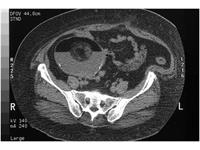

جستجو کلمه جستجو جستجو گروه بندی همه موارد مقالات » دانستنی های پزشکی زنان » رحم و تخمدان از تاریخ تاریخ صحیح نمی باشد. * تا تاریخ تاریخ صحیح نمی باشد. * انواع و چگونگی ایجاد اختلالات رحمی اختلالات رحمی به صورت مادرزادی و در اثر ژنتیک و ناهنجاری ساختمانی رحم در بعضی بیماران به وجود میآید. این اختلالات در اثر گذشت زمان باعث سقط مکرر جنین... تخمدان چیست و بیماریهای مربوط به آن تخمدانها دو غده تخم مرغی شکل هستند که در دو طرف رحم قرار گرفتهاند و از طریق لوله فالوپ به رحم متصل هستند. سندرم تخمدان پلیکیستیک چیست؟ زنان مبتلا به این بیماری علایم شایعی مانند اختلالات قاعدگی، علایم هیپرآندروژنیسم مانند پرمویی و آکنه، ریزش مو و نازایی دارند. بیماران در معرض عوارض جد... کیست درموئید تخمدان کیست در موئید تخمدان چیست و چه علتی دارد؟ آیا کیست درموئید مویی خطرناک است و باعث نازایی میشود؟ روش های درمانی کیست درموئید تخمدان به چه شکل است؟ بیماری آندومتریوز در زنان چیست؟ علائم و درمان آن آندومتریوز به معنی رشد بافت داخلی رحم در جایی بیرون از رحم است. لگن شایعترین محل بروز آندومتریوز است. فیبروم رحم چیست؟ علائم، علل و درمان آن فیبروم رحم رشد بیش از اندازهٔ بافت رحم در زنان در سن بچه داری است یا به عبارتی فیبروم رحم یا تومورخوش خیم عضلهٔ صاف رحم، شایعترین تومور لگنی در نزد زنا... پولیپهای رحم در خانمها پولیپهای رحم معمولا غیرسرطانی (خوش خیم) هستند، اگر چه بعضی از آنها سرطانیاند یا میتوانند سرطانی شوند. پولیپها در دیواره داخلی رحم رشد میکنند. رشد... دستگاه تولید مثل در زنان: آناتومی و عملکرد دستگاه تولید مثل زنان از اندامهای جنسی داخلی (در داخل لگن) و خارجی (خارج از لگن) تشکیل شده است. ساختارهای تولید مثل خارجی در زنان، ورود اسپرم به بدن... با انواع بیماریهای تخمدان آشنا شوید بیماریهای تخمدانی شامل کیستهای تخمدان، سرطان تخمدان، بی نظمی دوره های قاعدگی، سندرم تخمدان پلی کیستیک، نارسایی زودرس تخمدان و پیچ خورگی تخمدان میبا...